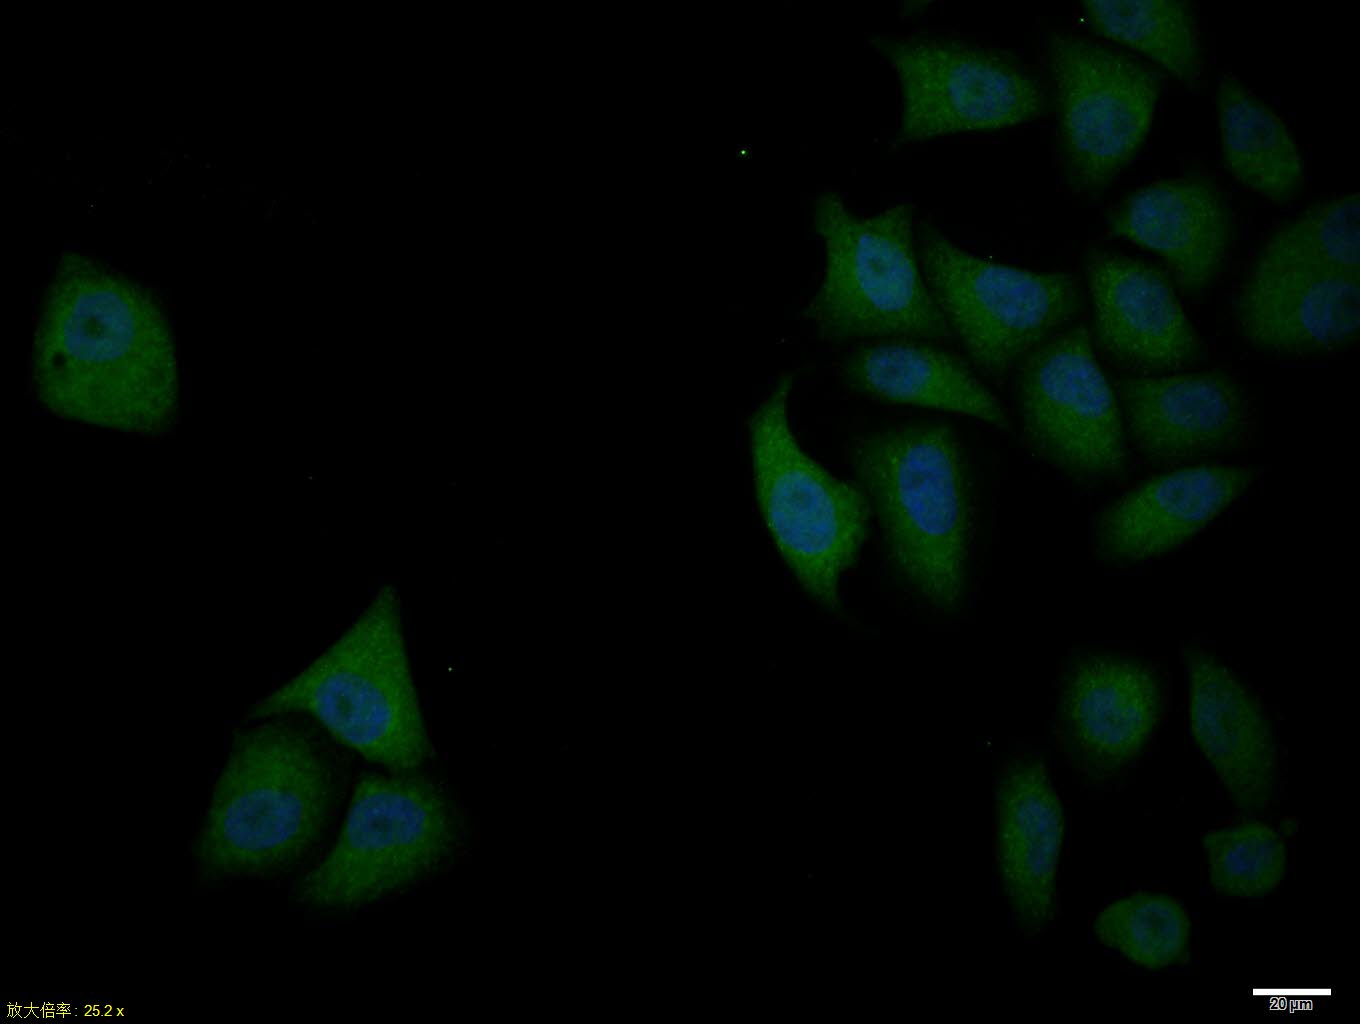

Primary Antibody (green line): Rabbit Anti-Bcl-xL antibody (bs-1336R)

Dilution: 1ug/Test;

Secondary Antibody : Goat anti-rabbit IgG-FITC

Dilution: 0.5ug/Test.

Protocol

The cells were fixed with 4% PFA (10min at room temperature)and then permeabilized with 0.1% PBST for 20 min at room temperature.The cells were then incubated in 5%BSA to block non-specific protein-protein interactions for 30 min at room temperature .Cells stained with Primary Antibody for 30 min at room temperature. The secondary antibody used for 40 min at room temperature. Acquisition of 20,000 events was performed.